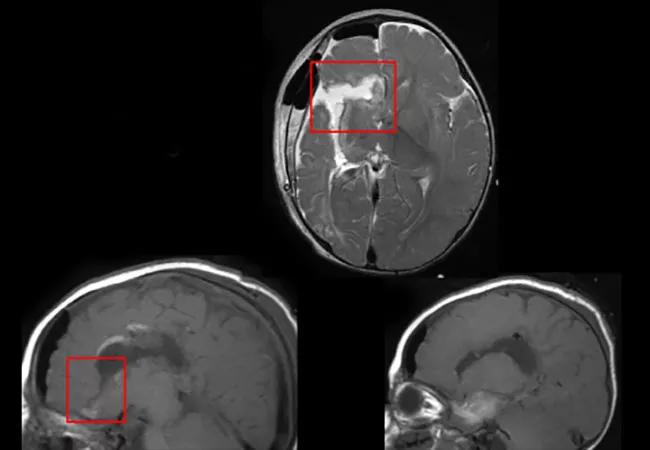

Her perinatal course was marked by preeclampsia, decreased fetal movement, reduced heart rate and premature birth. MRI subsequently revealed that she had suffered a perinatal right middle cerebral artery (MCA) infarction, with extensive cystic encephalomalacia. The images also showed subtle focal abnormality in the left frontal lobe, consistent with gliosis.

A right disconnective (“functional”) hemispherectomy is performed, in which the connections between the hemispheres are severed but the hemisphere left in place. No immediate complications are evident.

EEG now shows clear asymmetry, with all rhythms markedly reduced on the operated right side. She now has unilateral or hemi-hypsarrhythmia on the left — and only a few isolated spikes on the right. Furthermore, the ictal EEG patterns are also higher on the left, with an initial high-amplitude sharp wave followed by paroxysmal fast activity.

Interpreting post-hemispherectomy EEGs is challenging. Seizures may arise within focal areas of the operated side and then propagate to the contralateral side, where they show up on EEG. It is possible that her disconnection is incomplete, even though this is not apparent on MRI.

Despite the diagnostic challenges, complete (“anatomical”) hemispherectomy should be considered for continued seizures after a disconnective hemispherectomy, even if the side of seizure onset cannot be confirmed with EEG or MRI. EEG may show spread patterns on the contralateral side, and MRI may fail to reveal small nests of connected epileptogenic neurons.

In our case, although the side of seizure onset is impossible to determine with certainty based on the available evidence, it is decided to proceed with a complete hemispherectomy, allowing confidence that no residual tissue will remain in the right hemisphere.